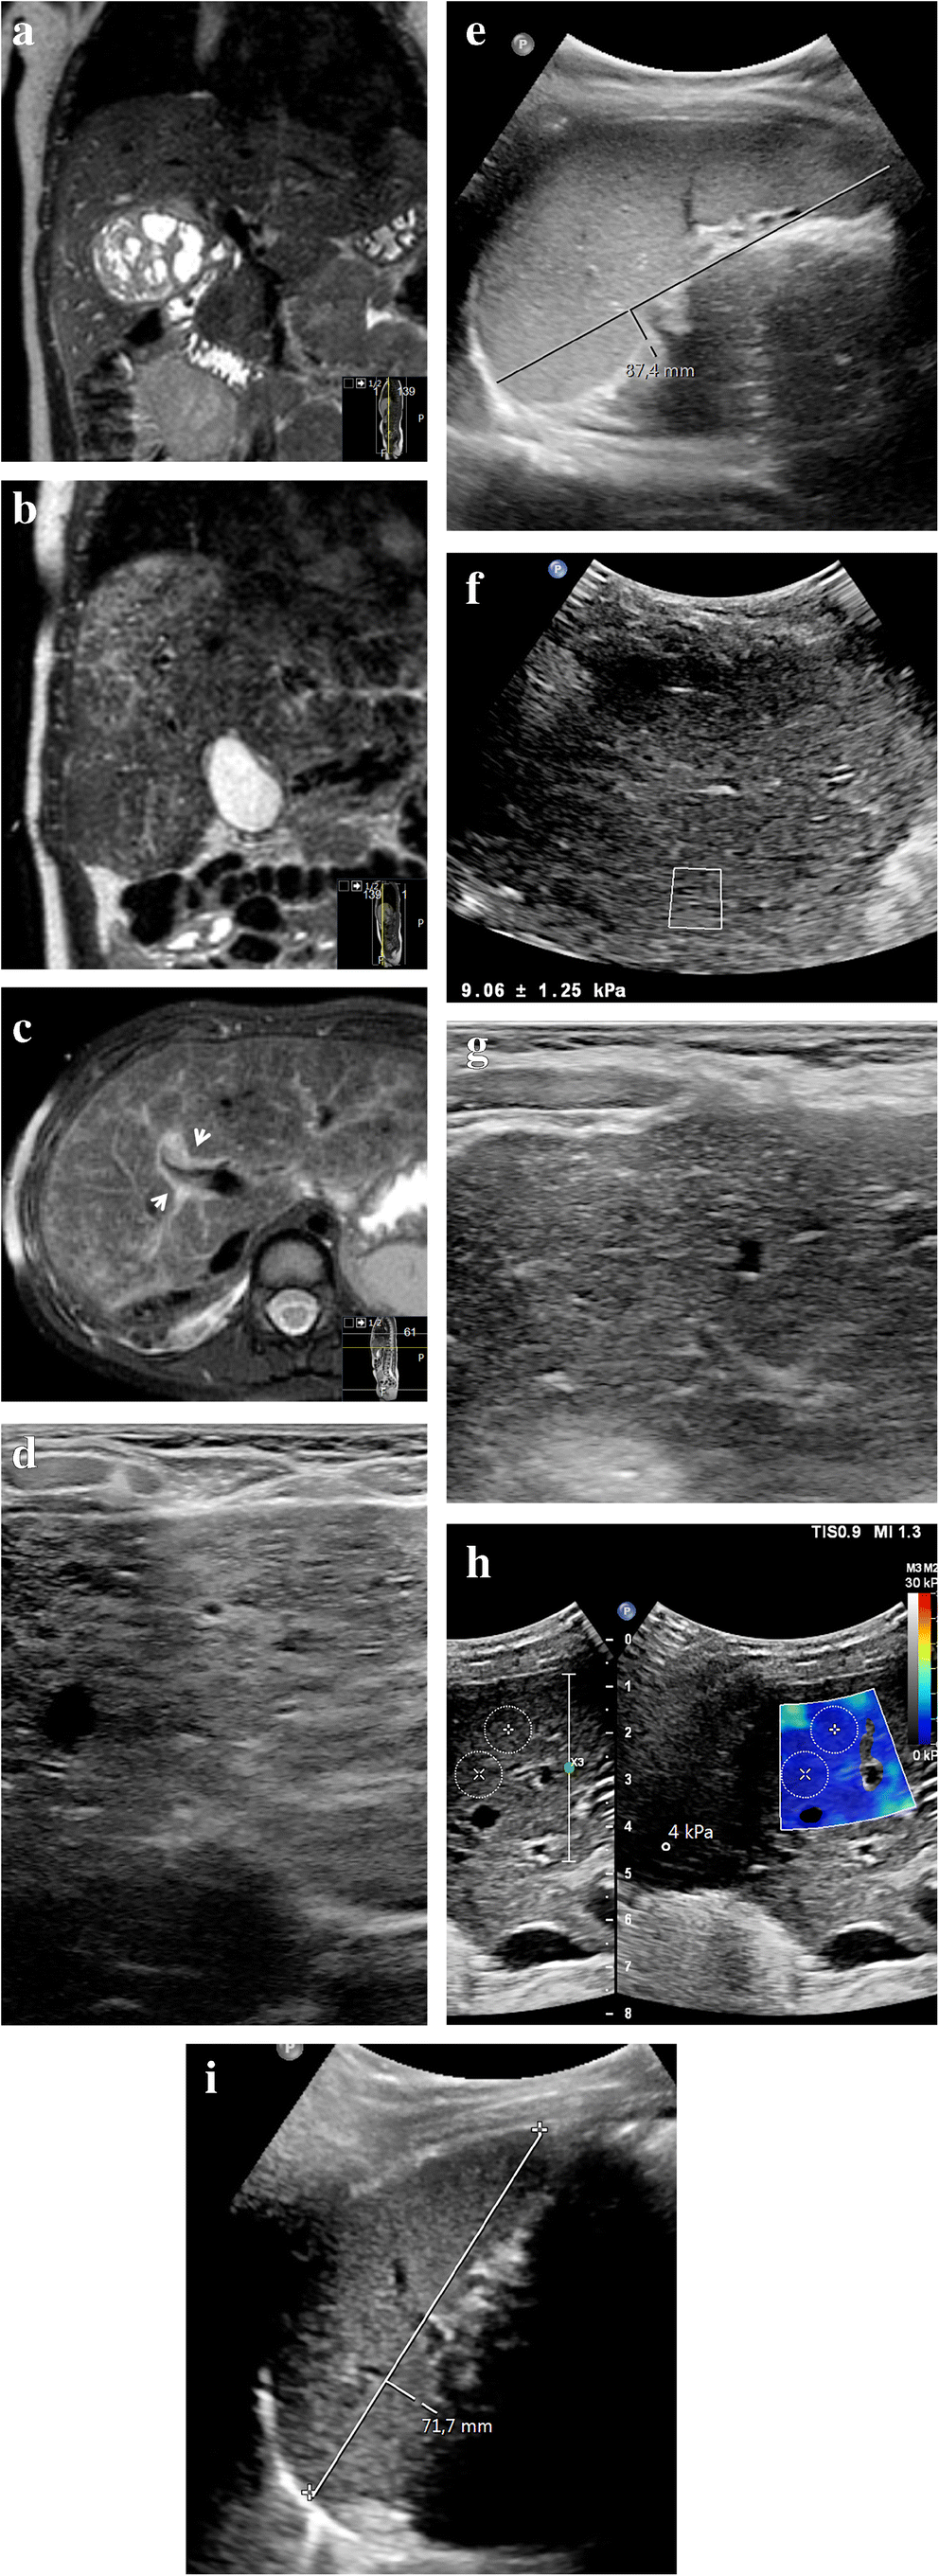

Follow-up

While most imaging abnormalities related to sinusoidal obstruction syndrome in children resolve spontaneously, some do not. We have summarized the multi-modality imaging spectrum of sinusoidal obstruction syndrome over time in Table 3. To illustrate the course of liver abnormalities, Fig. 7 shows follow-up images in a 3-year-old girl with stage 2 nephroblastoma, intermediate risk. An intraoperative liver sample in this patient showed confluent areas of acidophilic degenerated hepatocytes in the proximity of the central hepatic veins, a finding that could be in keeping with sinusoidal obstruction syndrome or chemotherapy-related toxic damage. After completing postoperative treatment with actinomycin D and vincristine, follow-up MRI and US showed enlargement of the liver and spleen with periportal edema, patchy heterogeneous liver parenchyma, minimal ascites and elevated liver stiffness — findings that could well be in keeping with experienced or ongoing mild sinusoidal obstruction syndrome, although there were no clinical signs or symptoms other than mildly elevated liver transaminases. On follow-up US imaging, all abnormalities normalized except for the heterogeneous liver parenchyma, which still persists after 2 years.

Fig. 7

Long-term liver abnormalities in a 3-year-old girl with stage 2 nephroblastoma, intermediate risk. a Coronal three-dimensional (3-D) T2-weighted turbo spin echo magnetic resonance (MR) image (repetition time [TR]/echo time [TE] 447/90 ms) shows the right renal tumor mass before treatment. An intraoperative liver sample showed confluent areas of acidophilic degenerated hepatocytes in the proximity of the central hepatic veins, a finding that could be in keeping with sinusoidal obstruction syndrome or chemotherapy-related toxic damage. b, c Follow-up imaging at the end of the postoperative treatment regimen with actinomycin D and vincristine. Coronal 3-D T2-weighted turbo spin echo MRI (b) (TR/TE 445/90 ms) and transverse T2-weighted fat-saturated multivane xd MRI (c) (TR/TE 3,294/67.1 ms) show enlargement of the liver from baseline (c), with diffuse patchy heterogeneous T2 hyperintensities and periportal edema (arrows). d A transverse high-resolution ultrasound (US) image (linear 12–5 MHz probe) of the liver shows heterogeneous liver parenchyma in keeping with the MRI. e A sagittal grey-scale US image shows an enlarged spleen of 8.7 cm. f An elastography measurement of the liver parenchyma via intercostal approach shows an elevated stiffness of 7.3 kPa (Epiq ElastPQ, Philips Healthcare, Best, The Netherlands). The patient had not experienced clinical signs of sinusoidal obstruction syndrome other than mildly elevated liver transaminases, with normal bilirubin. Hepatomegaly in combination with minimal free fluid (not shown) matches mild sinusoidal obstruction syndrome. No specific treatment for sinusoidal obstruction syndrome was given. g The liver parenchyma remains heterogeneous on follow-up US 2 years later (transverse high-resolution US image of the liver). h The elastography measurement (transverse image) of the liver normalizes to 4 kPa (Philips Epiq ElastQ) on the same follow-up US. i A sagittal grey-scale US image at follow-up shows that the size of the spleen has normalized